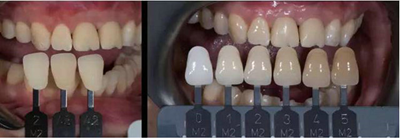

天然牙顏色分析:首先確定基礎(chǔ)顏色,A2色,觀察側(cè)切牙形態(tài)及顏色,頸部邊緣嵴有乳光效果,切緣伴有琥珀色。

將牙齒分為三部分,頸部邊緣飽和度高,切端伴有白斑

飾面瓷堆塑

牙齒形態(tài)修整

根據(jù)天然牙形態(tài)進(jìn)行牙冠形態(tài)修整、表面紋理再現(xiàn)和咬合關(guān)系調(diào)整

角度螺絲通道全瓷基臺(tái)一體冠制作完成

染色、上釉,再現(xiàn)天然牙的顏色特點(diǎn)。